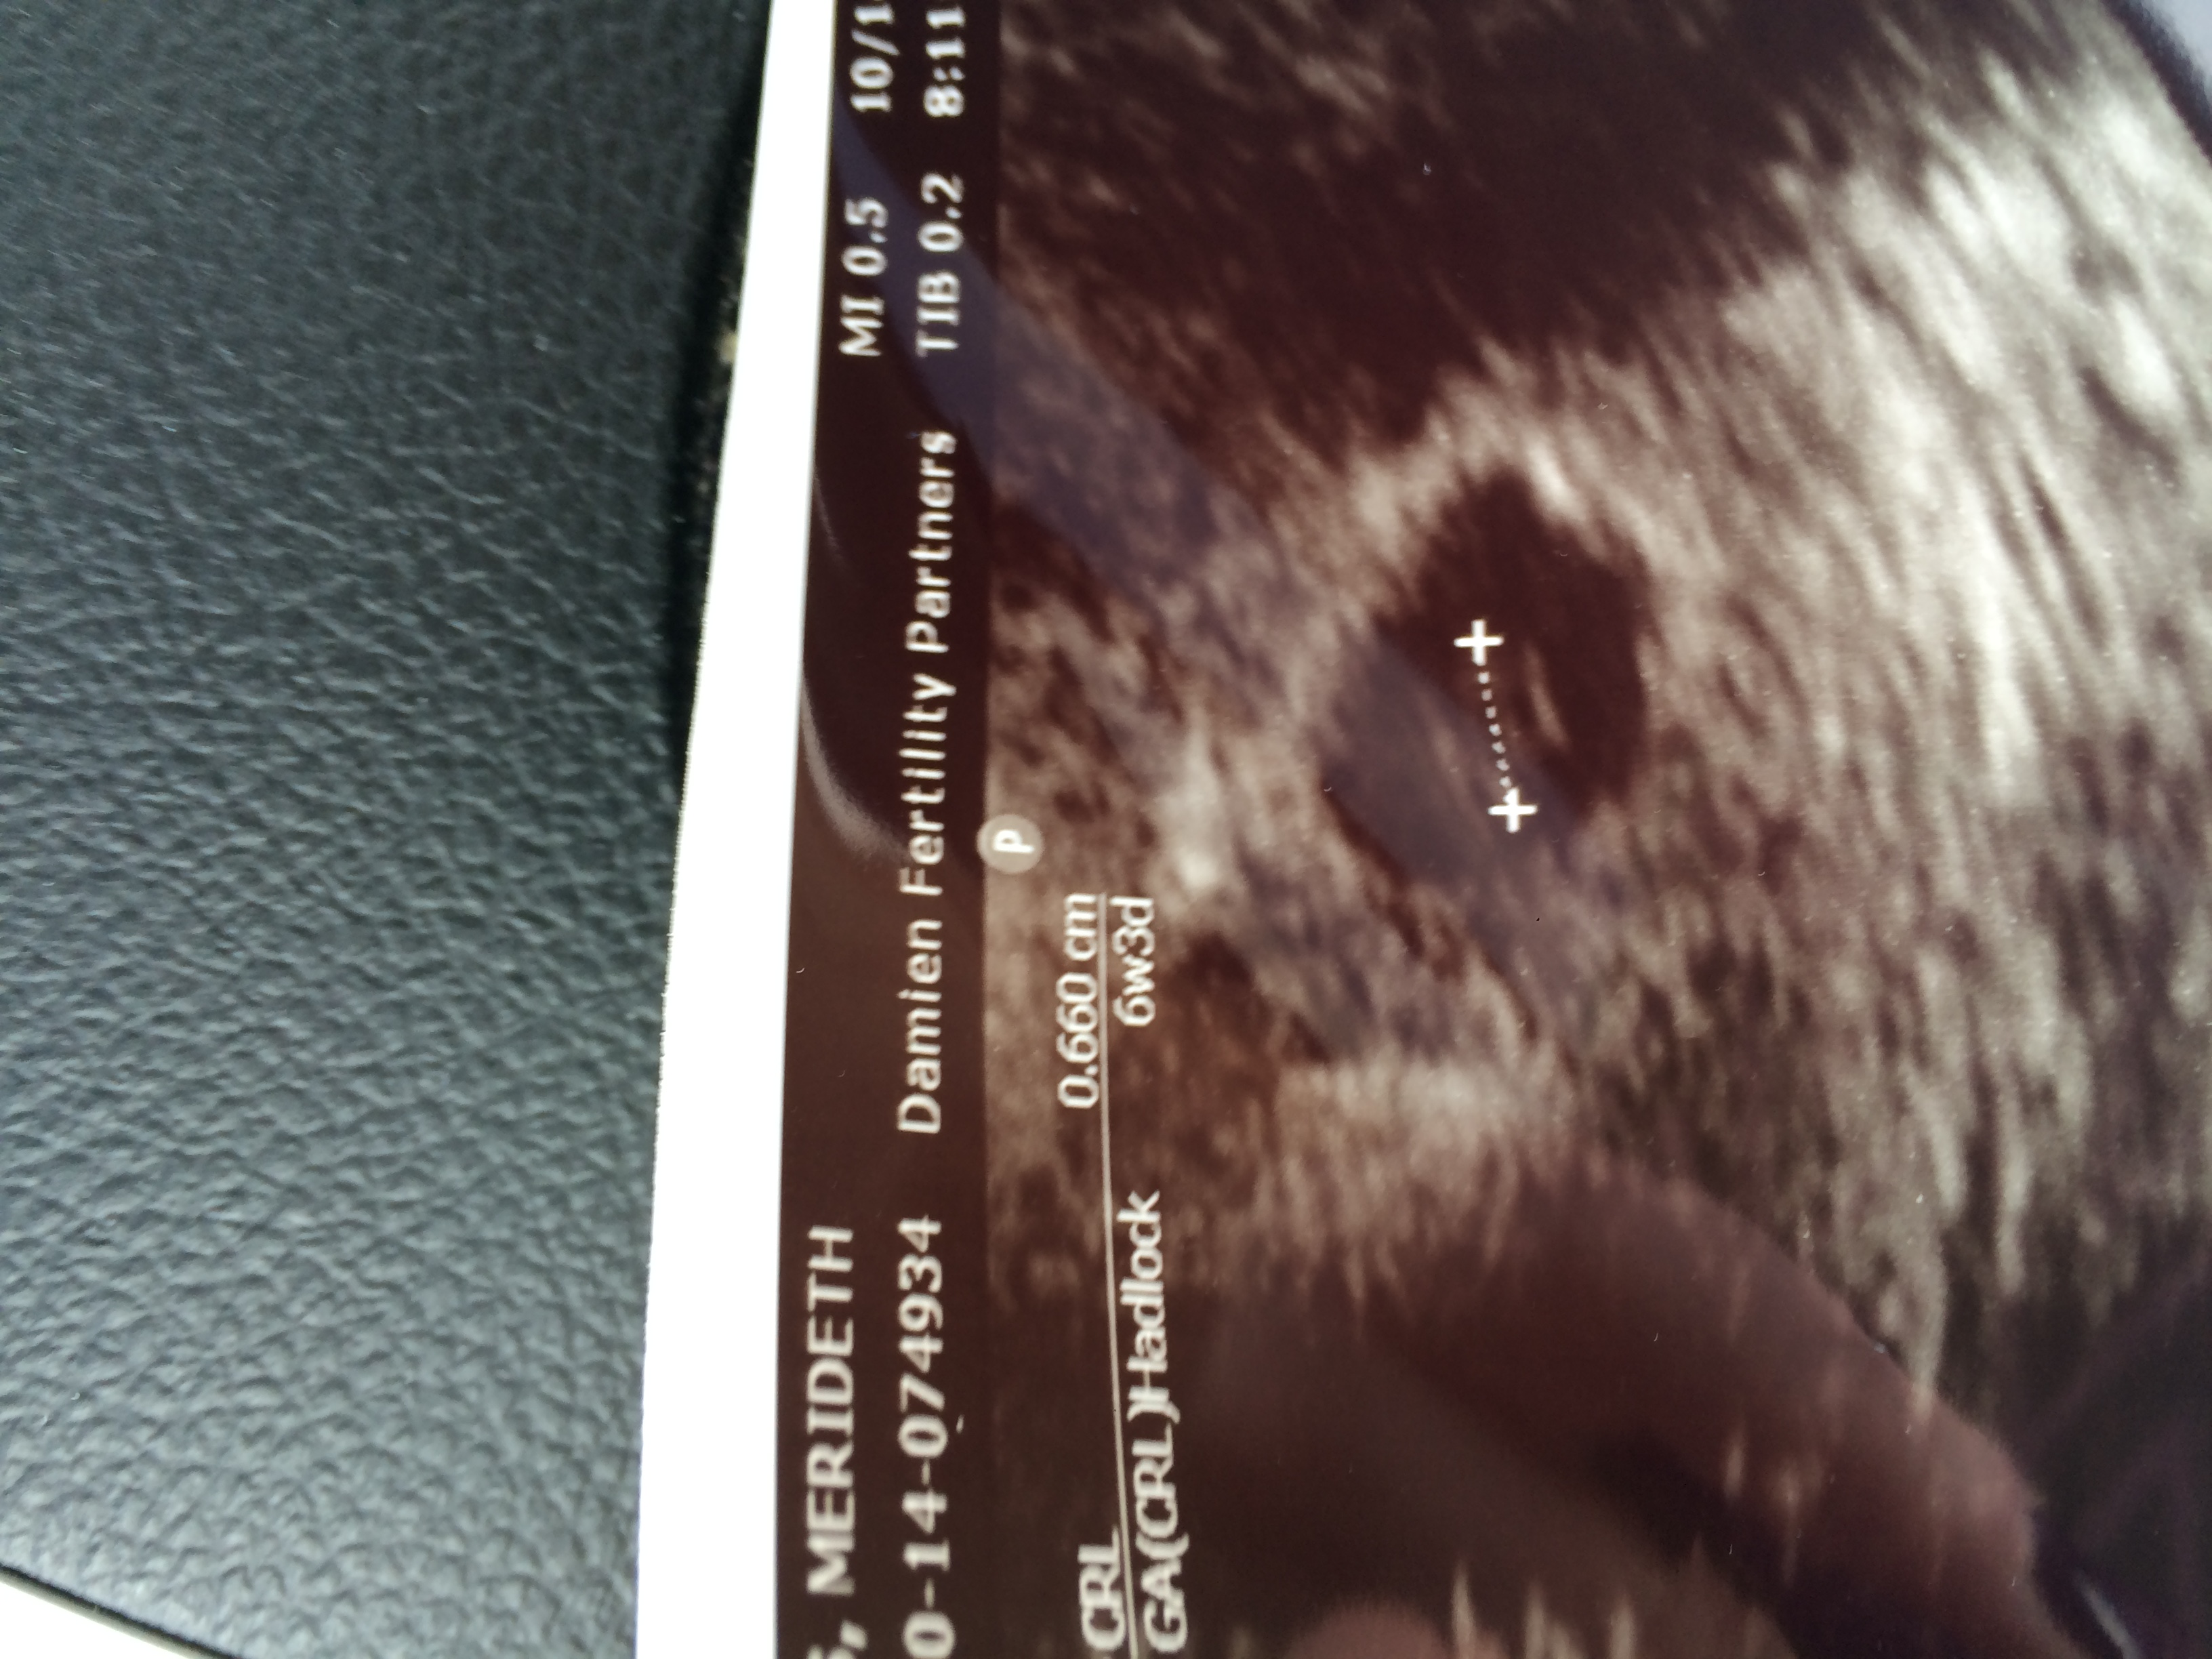

Hi all, I had some light brown spotting tues evening and Wednesday, I didn't have any yesterday or this morning, but the doc wants me to come in for an early u/s- it will be a little over 6 weeks, I am freaking out, wasn't mentally prepared for an US early Monday morning, I am half excited half dreading it- I hope everything is ok. Symptoms are getting stronger (nausea, boobs are very large, and stretching in the abdomen) so I feel ok in that sense. I'll let yall know how it goes!

Hi all, we had an early ultrasound this morning. Baby was measuring 6w1d-right on track and we saw the heartbeat!! So relieved, since we went in due to light brown spotting earlier last week. Everything looks good-next appt at 8w5d!